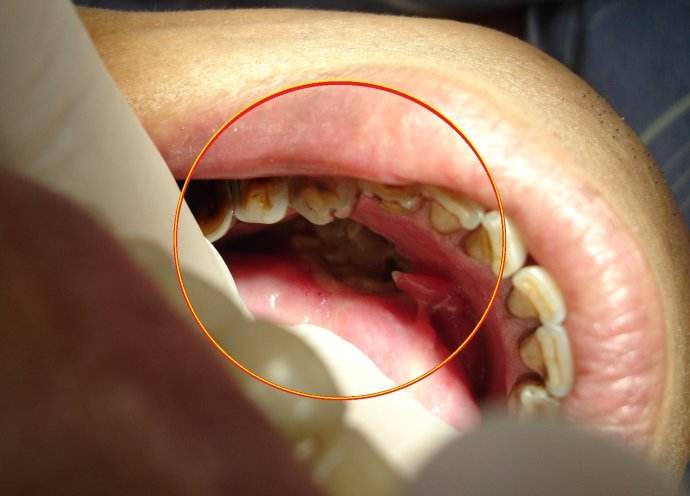

扁桃體癌圖 (69)